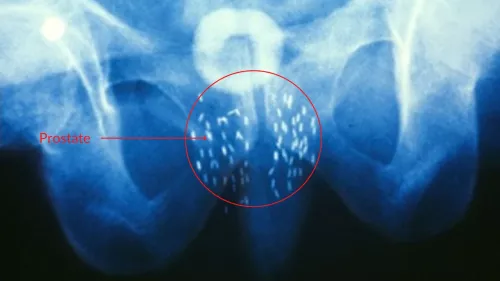

Pourquoi une curiethérapie peut impacter l’érection ?

Pourquoi une curiethérapie peut impacter l’éjaculation ?

Curiethérapie et sexualité anale, quels conseils ?